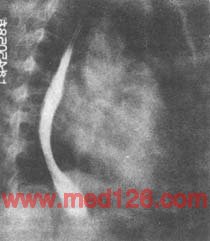

图2 风湿性心脏病 二尖瓣狭窄

心脏X线右前斜位:食管下段受左心房压迫向后移位,肺动脉圆椎隆起